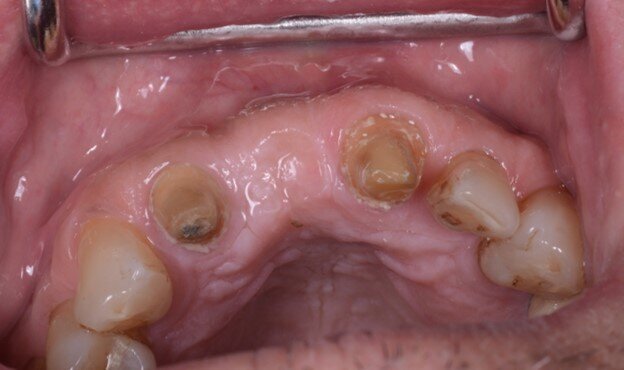

Il paziente era stato precedentemente sottoposto a un intervento di chirurgia rigenerativa con innesto sintetico (stampato in 3D in idrossiapatite/ beta-tricalcio-fosfato) tipo onlay custom-made nella zona dell’incisivo centrale superiore di destra. A 6 mesi dall’intervento, il paziente era pronto a ricevere l’impianto. Per lo studio del caso, il paziente veniva sottoposto a cone beam computed tomography (CBCT) (CS9600, Carestream Dental) (Fig. 1) ed a scansione dell’arcata dentaria di riferimento con potente scanner intraorale (DEXIS IS 3800w, DEXIS) (Figg. 2, 3).

Fig. 2_Scansione intraorale dell’arcata (DEXIS IS 3800w, DEXIS), visione frontale.

Fig. 3_Scansione intraorale dell’arcata (DEXIS IS 3800w, DEXIS), visione occlusale.